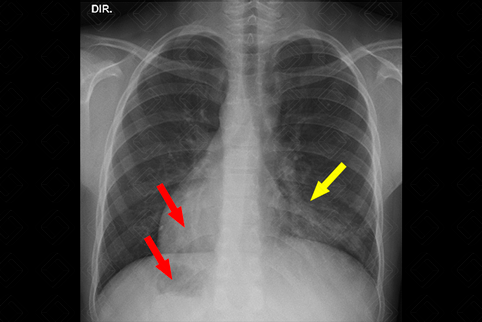

Texto alternativo para a imagem Figura 2. Créditos: Dra. Elazir Mota - Rio de Janeiro/RJ

Descrição da figura 2: Tomografia computadorizada do tórax confirma o situs inversus e torna mais evidente as bronquiectasias à esquerda (no que seria o correspondente ao lobo médio – seta vermelha).

• Tomografia computadorizada do tórax: A caba sendo solicitada para confirmação do quadro, onde notamos com mais clareza as bronquiectasias e avaliamos adequadamente seu acometimento, sendo mais comum no lobo médio, língula e lobos inferiores (f igura 2) .